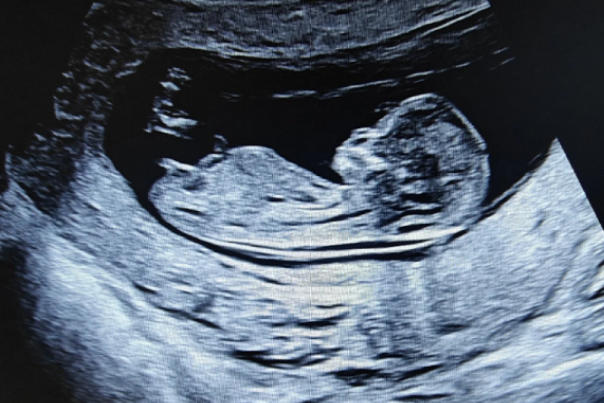

在孕11周到13周+6天这个特殊的时间窗口要做NT检查。NT值在正常范围内,算是闯过第一道关;一旦数值偏高或被告知NT不过,紧张、焦虑、不安的情绪便会瞬间涌上心头。为什么会出现NT增厚?是胎儿哪里出了问题?这些问题成了准妈妈们夜不能寐的根源。事实上,NT作为早期排畸筛查的重要指标,它的异常确实需要引起重视,但绝不意味着胎儿就一定有问题。了解NT增厚背后的原因,才能理性面对、从容应对。

NT,即胎儿颈后透明带厚度,指的是胎儿颈部后方皮下积液的厚度。在孕早期,胎儿的淋巴系统尚未发育完善,少量液体积聚在颈部是正常现象。但当NT值超过正常范围时,医学上称为NT增厚。这个增厚的背后,可能隐藏着多种原因,从无需干预的生理性因素到需要警惕的病理性问题,跨度很大。